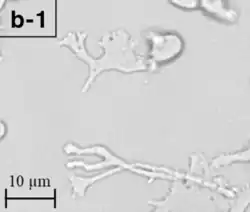

| A Balamuthia mandrillaris cyst | |

B. mandrillaris is a free-living, heterotrophic amoeba, consisting of a standard complement of organelles surrounded by a three-layered cell wall (thought to be made of cellulose or a similar polysaccharide[8]), and with an abnormally large cell nucleus. On average, a Balamuthia trophozoite is about 30 to 120 μm in diameter. The cysts fall around this range, as well.[9]

Balamuthia's lifecycle, like the Acanthamoeba, consists of a cystic stage and a non-flagellated trophozoite stage, both of which are infectious, and both of which can be identified in the brain tissue on microscopic examination of brain biopsies performed on infected individuals. The trophozoite is pleomorphic and uninucleated, but binucleated forms are occasionally seen. Cysts are also uninucleated, possessing three walls: an outer thin irregular ectocyst, an inner thick endocyst, and a middle amorphous fibrillar mesocyst.[10]

Biopsies of skin lesions, sinuses, lungs, and the brain can detect of B. mandrillaris infection. The amoeba cannot be cultured on an agar plate coated with E. coli because, unlike Naegleria or Acanthamoeba, Balamuthia mandrillaris does not feed on bacteria. Instead, Balamuthia must be cultured on primate hepatocytes or human brain microvascular endothelial cells.[15] Formalin-fixed paraffinized biopsy specimens may indicate Balamuthia trophozoites in the perivascular space. The cysts can be visualized by calcofluor white, which binds to polysaccharides on the cyst wall. Trophozoites appear circular during infection.[14]